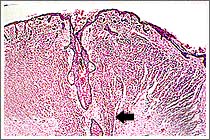

先天的色素細胞痣沿著毛囊分佈至皮下層,不適合用雷射治療